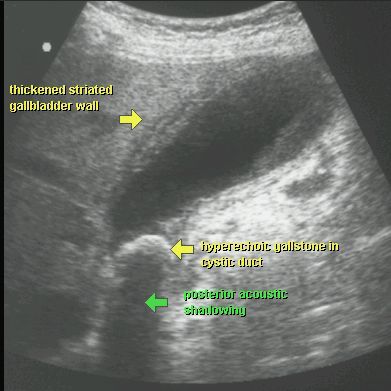

KAMICA PĘCHERZYKA ŻÓŁCIOWEGO Z ZAPALENIEM

USG